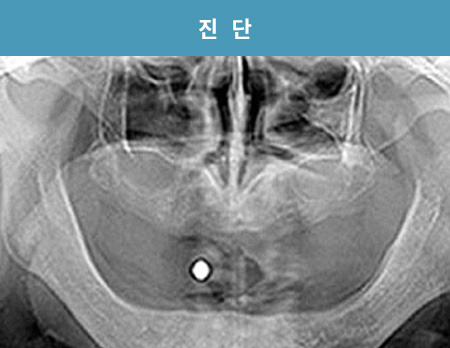

전북 외곽 지역에서 먼 걸음 해주신 환자분입니다

치아 손실로 오랜 기간 불편함을 겪으셨고, 잇몸뼈 흡수가 진행된 상태였습니다.

정밀 진단을 통해 잔존 치조골을 평가하고, 풀아치 임플란트 계획을 세워 단계적으로 치료를 진행했습니다.